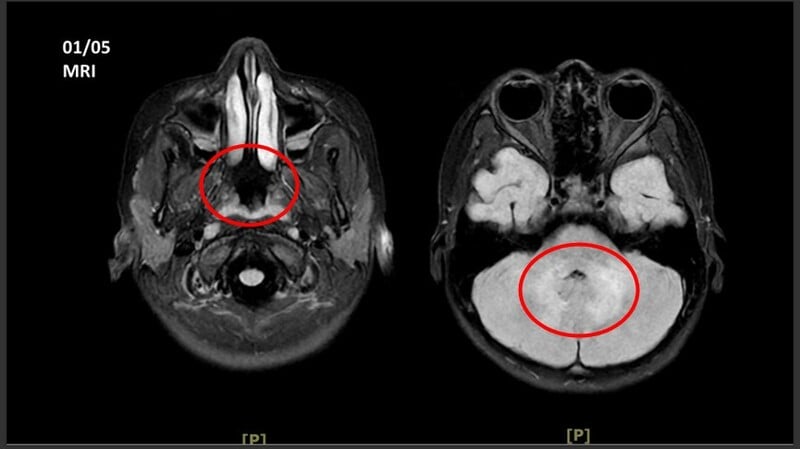

王傳育主任指出,女童當時血壓明顯偏高,心跳也較慢,醫療團隊擔心已有腦壓升高或顱內病變,立即安排住院,並同步給予降低腦壓治療與核磁共振掃描。檢查結果顯示,小腦、視丘及大腦白質、皮質下都可見異常訊號,符合急性散播性腦脊髓炎的影像表現。